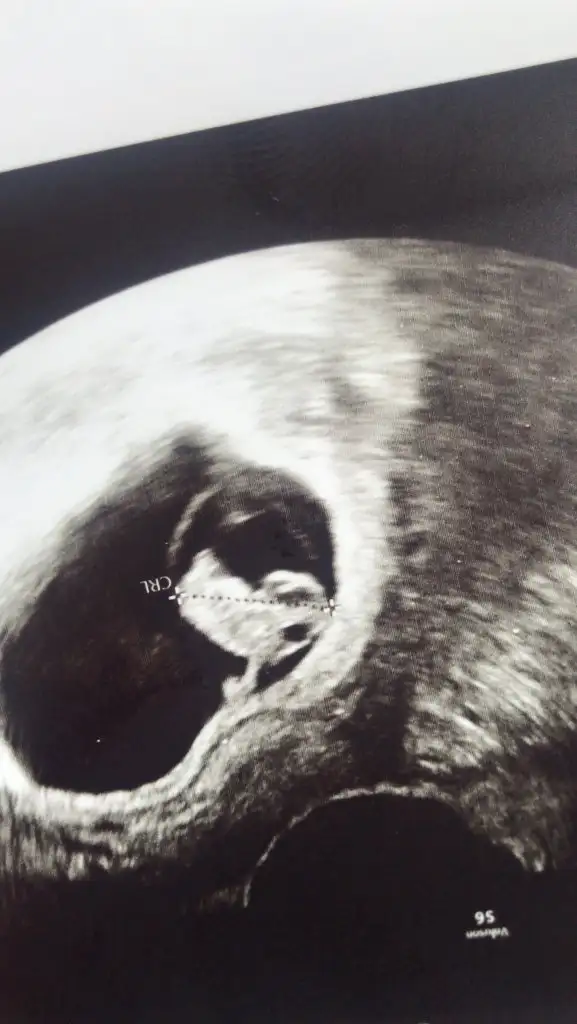

Kollar bacaklar açık yeni pozumuz heyecan dorukta hala tahmini olan yokmu?

Eki Görüntüle 2798871 Kollar bacaklar açık yeni pozumuz heyecan dorukta hala tahmini olan yokmu?

Canım hayırlısı olsun sağlıklı sıhhatli doğsun. Ben kıza benzettim. Kalça kemiğinin Orda herhangi bir çıkıntı yada torba göremedim. Kız diye tahmin ediyorum. Öğrendiğinde yazarsan sevinirim

Ayy gercekden mi Allahtan gelene boynumuz ince ama kız istiyor eşim karnımı goren erkek diyor ama bu sitede bilen kisiler hep kız dedi kurbaga gbi yatmıs bizde anlayamadık insallah söz haber edicem